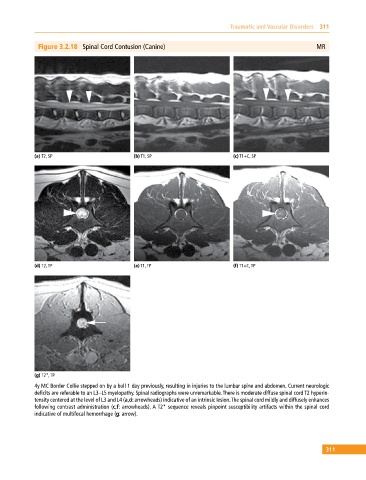

Figure 3.2.18 Spinal Cord Contusion (Canine) MR

(a) T2, SP (b) T1, SP (c) T1+C, SP

(d) T2, TP (e) T1, TP (f) T1+C, TP

(g) T2*, TP

4y MC Border Collie stepped on by a bull 1 day previously, resulting in injuries to the lumbar spine and abdomen. Current neurologic

deficits are referable to an L3–L5 myelopathy. Spinal radiographs were unremarkable. There is moderate diffuse spinal cord T2 hyperin-

tensity centered at the level of L3 and L4 (a,d: arrowheads) indicative of an intrinsic lesion. The spinal cord mildly and diffusely enhances

following contrast administration (c,f: arrowheads). A T2* sequence reveals pinpoint susceptibility artifacts within the spinal cord

indicative of multifocal hemorrhage (g: arrow).